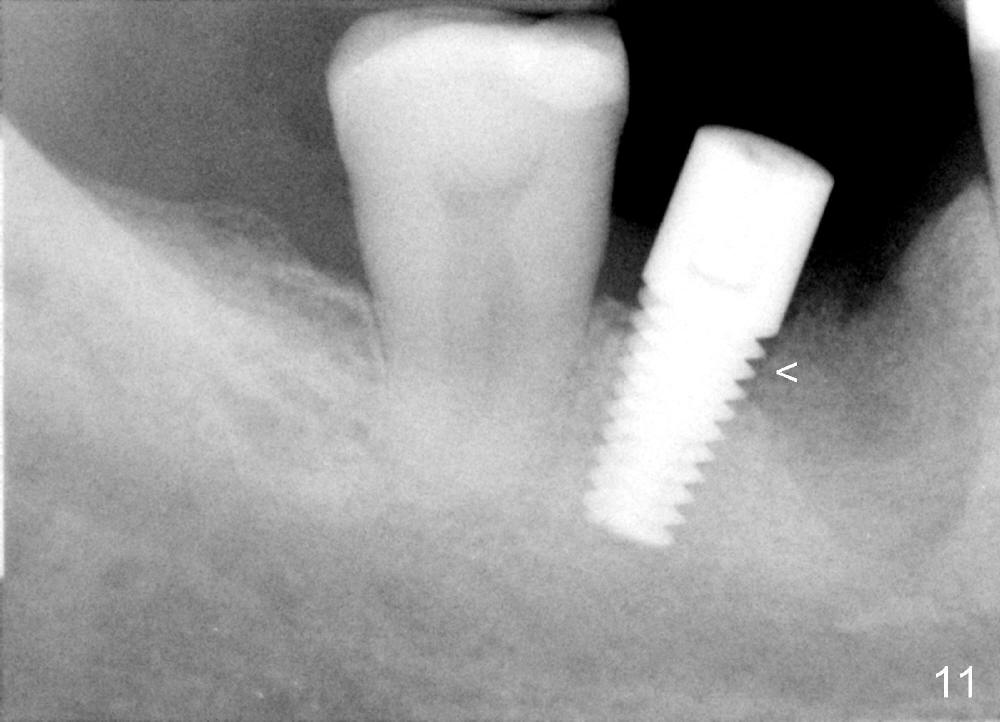

When the perio dressing is removed in office 24 days postop (Fig.9), the rough surface of the implant (R) is exposed buccally.  Normally the smooth surface should contact the gingiva (S).   Lingually implant/gingiva position is within normal limit (Fig.10).  The patient returns for restoration 4 months postop (Fig.11,12).  There is bone formation in the mesial socket and new bone appears to have grown toward the implant (Fig.11 <).  A straight abutment appears to be in the middle of the edentulous space (Fig.12 A).   But it is difficult to seat the crown.  Three months post cementation, the patient complains of food impaction mesially (Fig.10 ^), although bone density continues to increase in the mesial socket and there is no mesial coronal thread exposure (*).  Retrospectively the implant should be tried to be placed in the septum as much as possible to have a favorable restorative axis (Fig.14).  The crown is re-fabricated with larger mesial contact area.  It is temporarily cemented because of slightly loose distal contact (Fig.15).  A few days later, the patient requests permanent cementation, because although the distal contact is loose, it is easy to remove food.  Mesial food impaction is less likely, but it is more difficult to be removed.